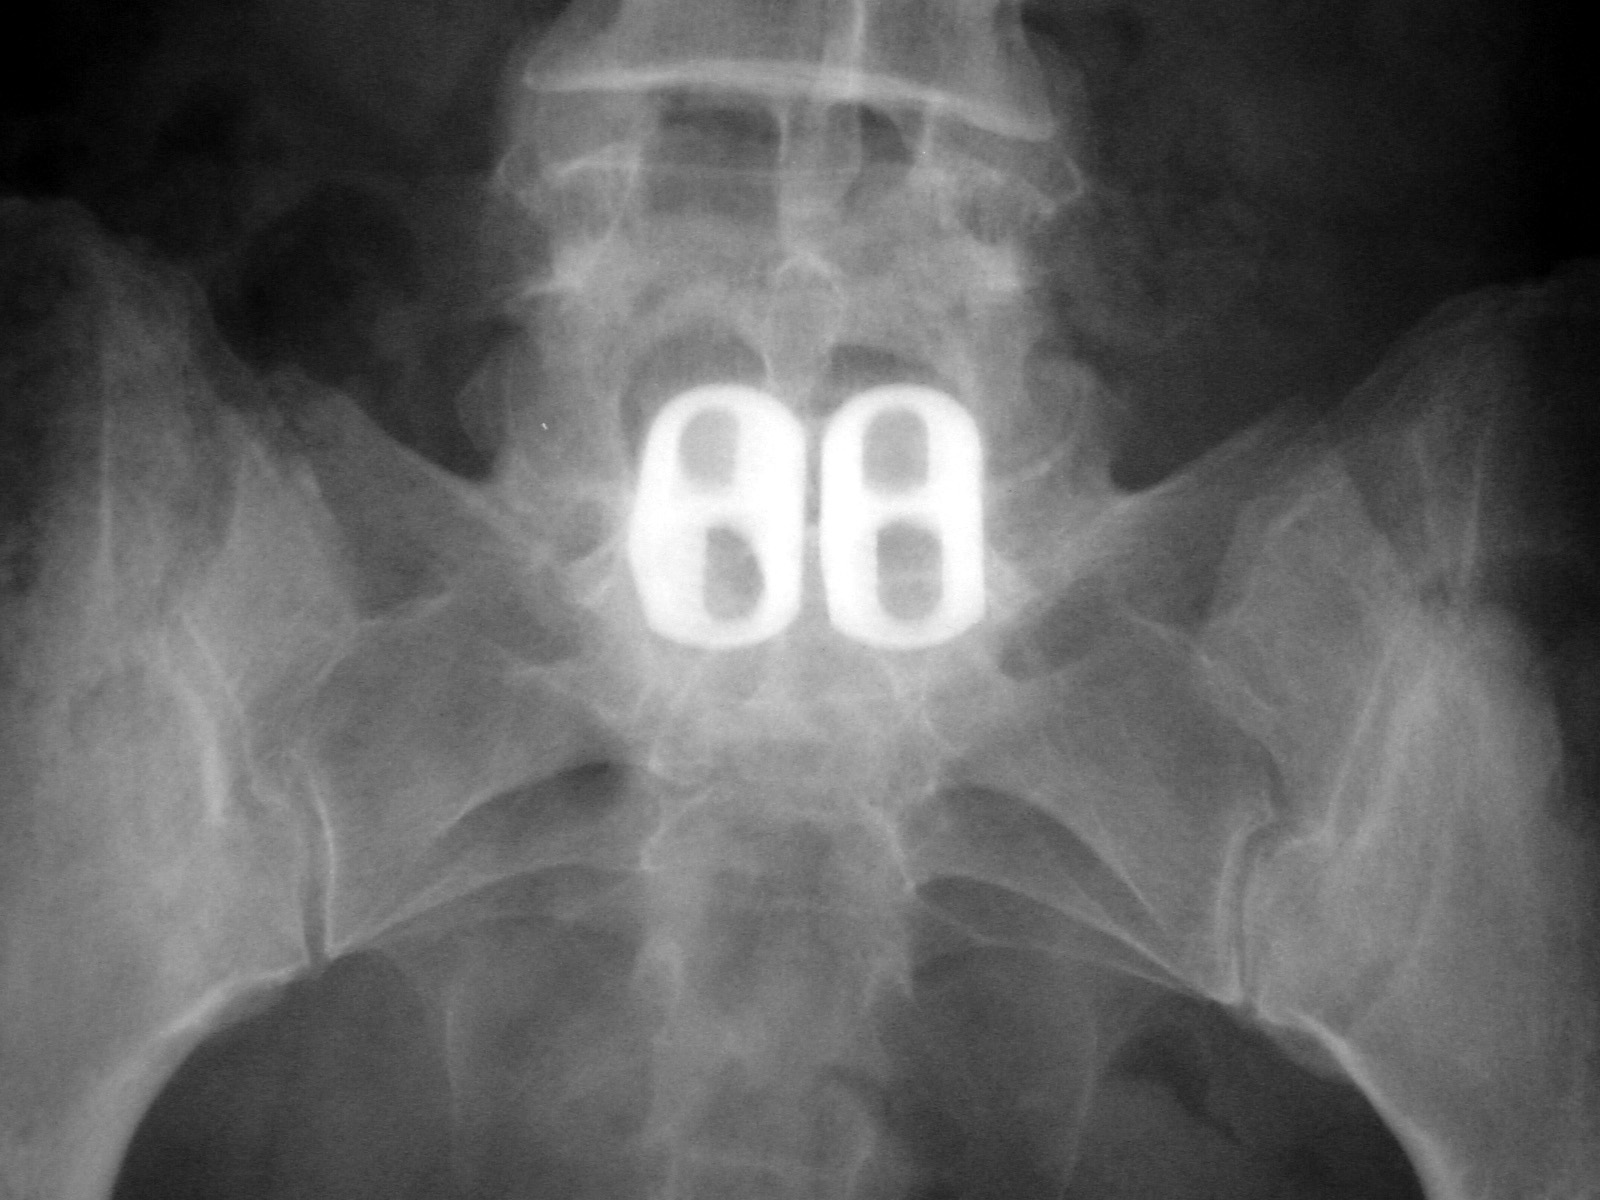

Intervertebral disc space cage Image Disc Spacer Device Radiology Device placed in the intervertebral space to restore disc height and facilitate bone growth to promote intervertebral fusion [2, 7]. As in the cervical spine, fusion consists of placement of graft material and an interbody. They can be used in various. The appearances are varied with the. The procedure involves bilateral partial laminectomies followed by diskectomy. Spinal instrumentation hardware refers. Disc Spacer Device Radiology.

Medical Devices of the Neck and Spine an imaging guide Disc Spacer Device Radiology They can be used in various. Spacer devices are often place either in isolation or along with anterior fixation following cervical disc surgery. Spinal instrumentation hardware refers to various types of implants used for fixation in spinal surgery. The procedure involves bilateral partial laminectomies followed by diskectomy. Device placed in the intervertebral space to restore disc height and facilitate bone. Disc Spacer Device Radiology.

Comparing the Bridge‐Type Zero‐Profile Anchored Spacer (ROI‐C Disc Spacer Device Radiology Device placed in the intervertebral space to restore disc height and facilitate bone growth to promote intervertebral fusion [2, 7]. Spacer devices are often place either in isolation or along with anterior fixation following cervical disc surgery. Spinal instrumentation hardware refers to various types of implants used for fixation in spinal surgery. A cervical disc replacement (also known as a. Disc Spacer Device Radiology.